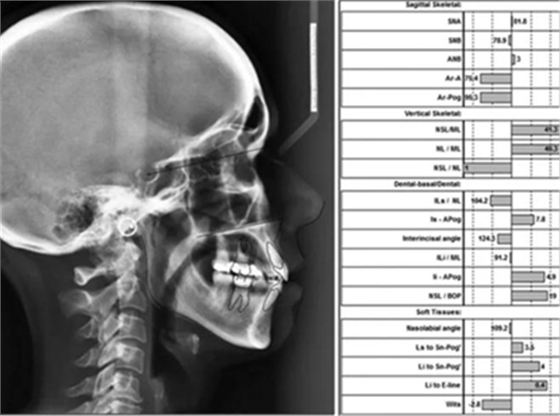

頭影測(cè)量分析,SNA角84°,ANB角6°,高角型,詳見(jiàn)下表。

患者側(cè)貌改善,下唇唇肌緊張消失,上下唇可自然閉合。磨牙及尖牙關(guān)系糾正至I類(lèi),覆合覆蓋正常。上下頜弓型糾正至卵圓形,牙弓寬度增加。頭影測(cè)量分析示SNA角81.8°,ANB角3°。頭影測(cè)量重疊圖示下頜骨向后旋轉(zhuǎn),垂直面高度略有增加。